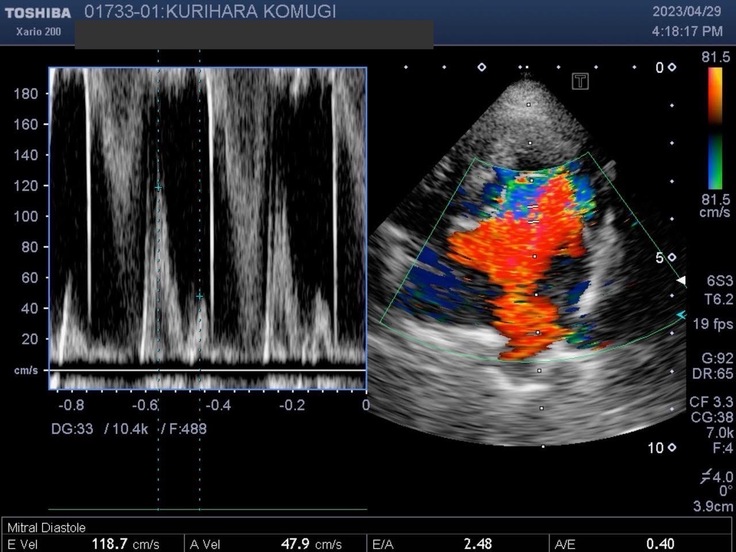

▽エコー写真

※かかりつけの動物病院からの掲載許可をいただいています。

※循環器専門病院からの掲載許可をいただいています